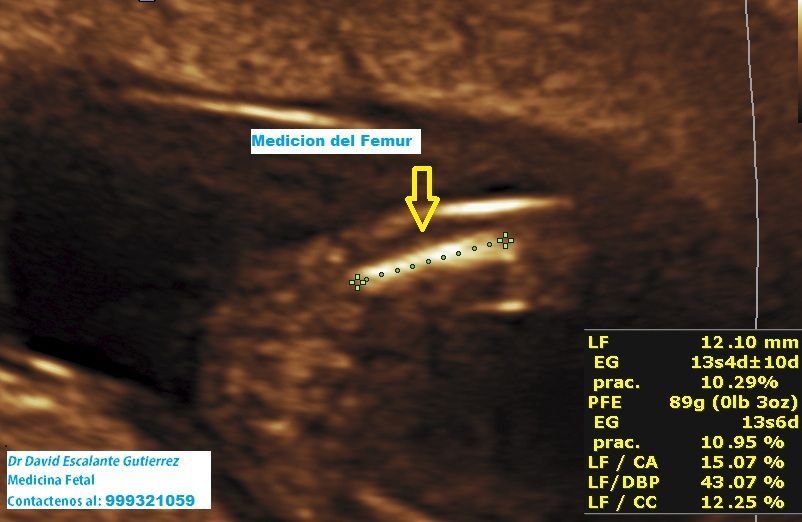

Realizamos las ecografías de viabilidad del embarazo, genética, morfológica, de bienestar fetal, ecocardiografías fetales, así como procedimientos invasivos como biopsia de vellosidades coriales y amniocentesis.